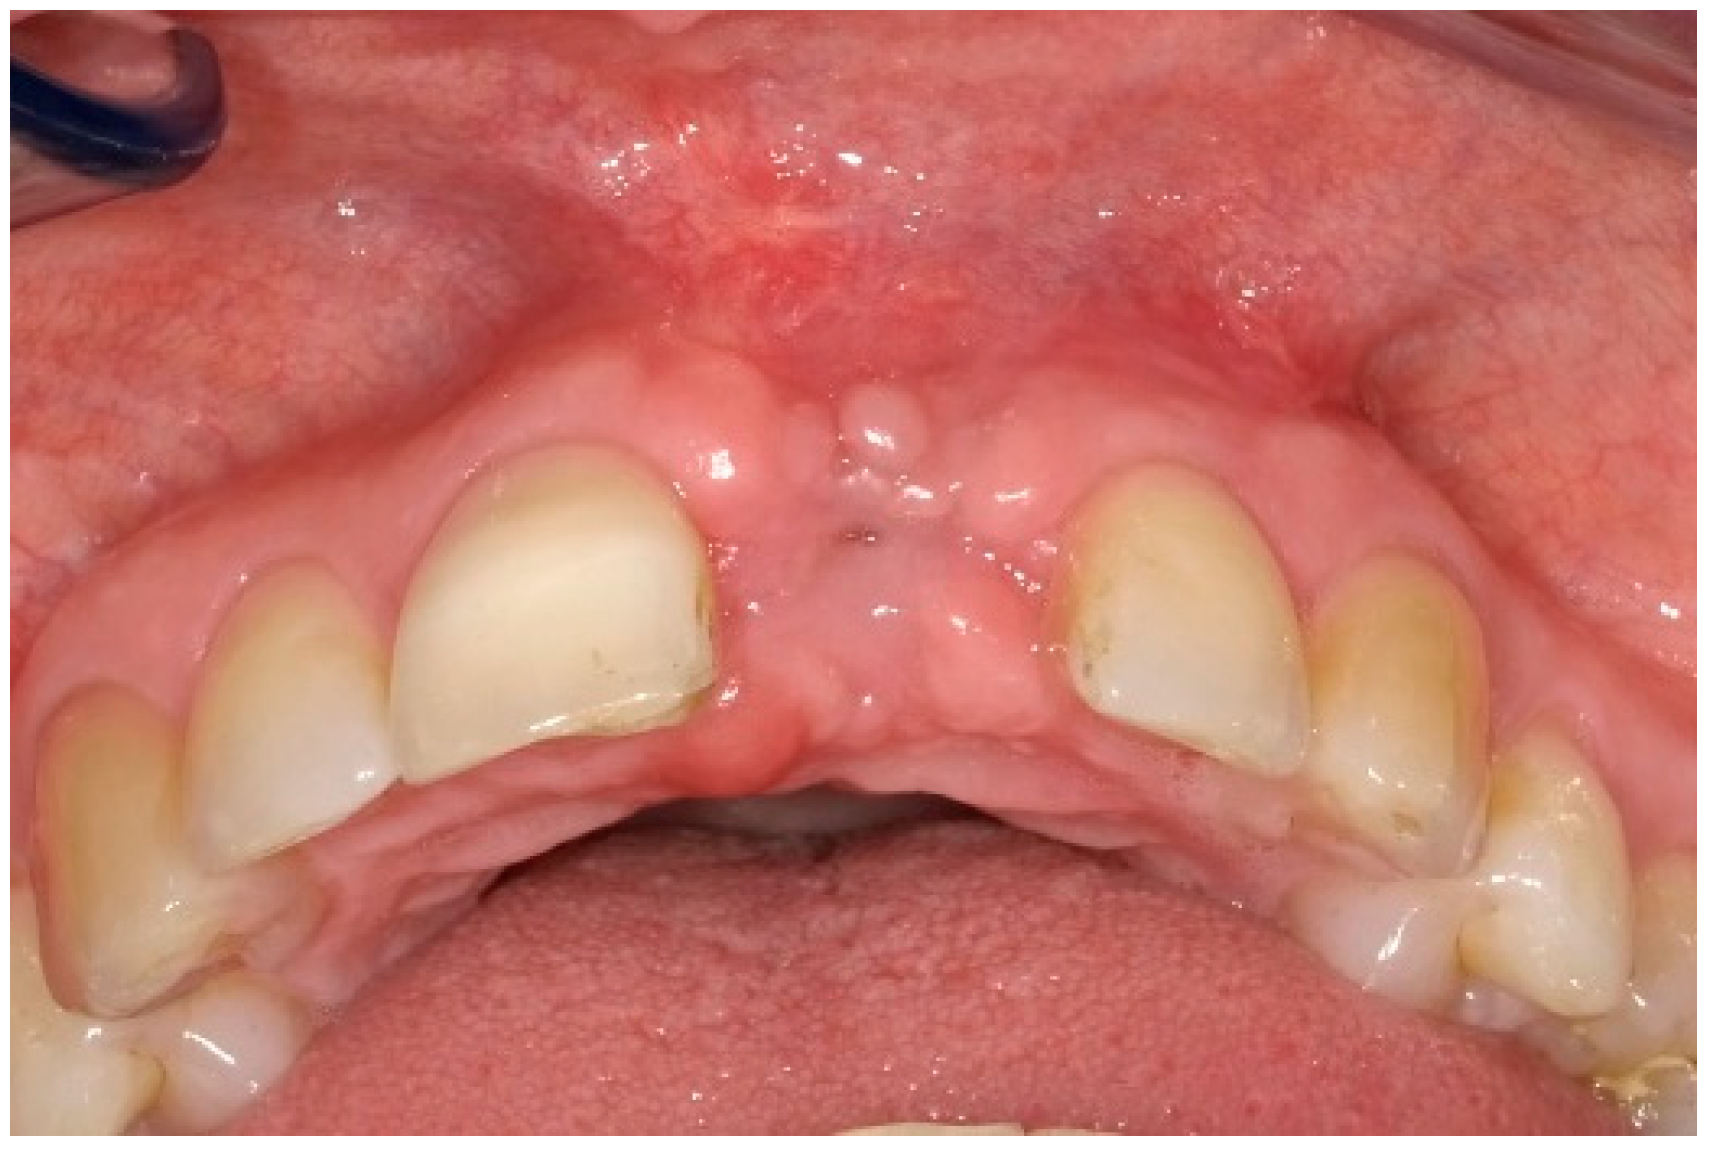

6. Follow-Up

7. Outcomes